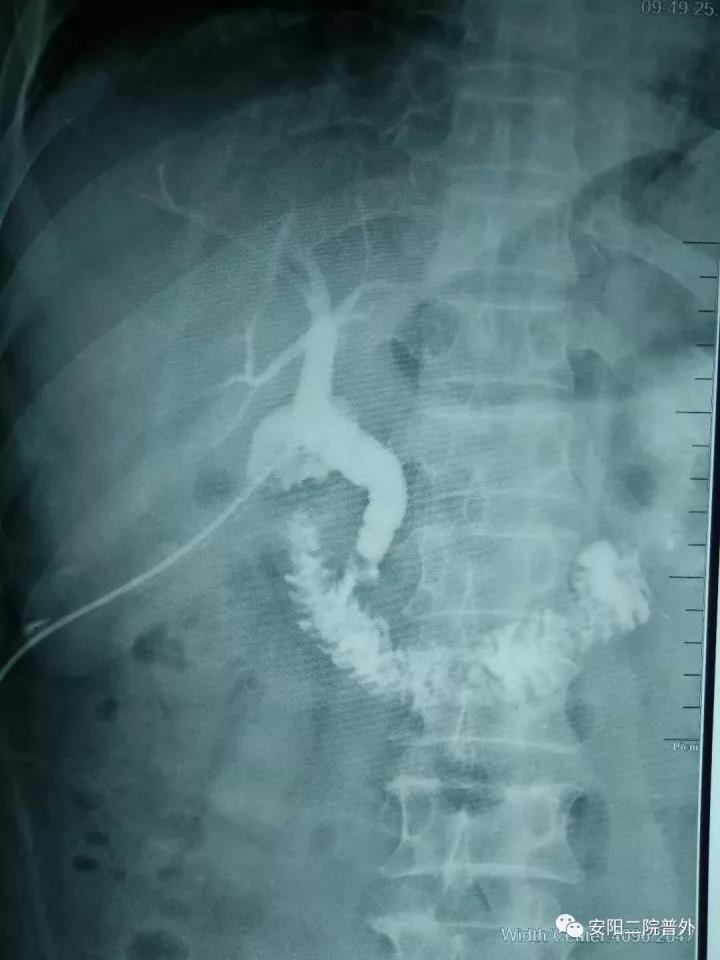

該例患者男性,52歲,外院行“膽囊切除+膽總管探查+T管引流術(shù)”,術(shù)后兩個(gè)月T管造影示:造影劑排入十二指腸受阻,膽總管擴張,膽總管下段見(jiàn)略低密度影,考慮膽總管下段結石?;颊哂诙嗉胰揍t院就診,因結石較大病情復雜未能入院治療。而后患者慕名找到普外科孟鈺主任,孟主任綜合評估后收住院,完善檢查后行膽道鏡檢查:術(shù)中見(jiàn)膽總管下段結石嵌頓,直徑約1.5cm,抓鉗及取石籃取石失敗,遂與泌尿外科張新軍主任聯(lián)合,行膽總管結石鈥激光碎石術(shù),將結石粉碎成小塊結石和粉末狀結石,取出小塊結石,將粉末狀結石沖洗入十二指腸,手術(shù)順利。目前患者康復出院。

內鏡下的膽總管結石

取石前